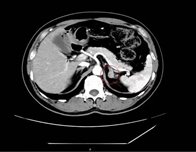

肾上腺CT正常表现

1.形态:形态各异;右侧:斜线状、倒“V”、倒“Y”形;左侧: 倒“V”、倒“Y”形或三角形;三维重建呈叶状。

2.大小: 侧支厚度<10mm;侧支厚小于同侧膈肌脚,面积小于150mm。

3.密度: 均匀,边缘光滑,无外凸结节。

4.强化: 均匀,边缘光滑。

肾上腺腺瘤CT表现

1.肾上腺腺瘤发生于肾上腺皮质,含脂质;

2.直径多小于3cm;

3.CT值<10HU;

4.出血、坏死、囊变少见;5.CT增强:早期快速廓清